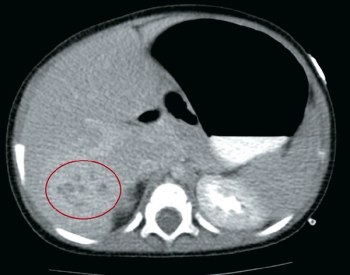

A 7-month-old girl presents to her pediatrician’s office with a 1-week history of fevers and upper respiratory symptoms. What's the diagnosis?